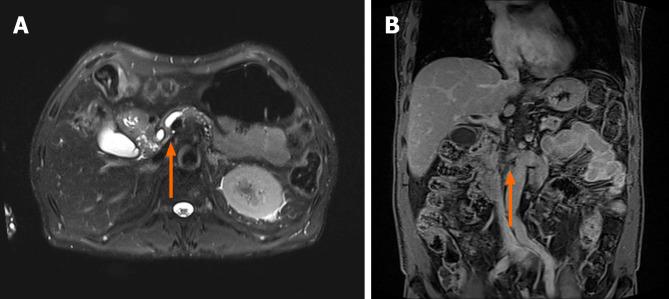

A 63-year-old man presented with persistent abdominal pain and weight loss. Diagnosis: Laboratory findings revealed elevated carbohydrate antigen 19-9 (5920 U/mL) and carcinoembryonic antigen (23.7 ng/mL) levels. Magnetic resonance imaging of the pancreas revealed an approximately 3 cm ill-defined space-occupying lesion in the inferior aspect of the head, with severe encasement of the superior mesenteric artery. Pancreatic ductal adenocarcinoma was confirmed after pathological examination of specimens obtained by EUS-TS using the fanning method. Interventions and outcomes: The following day, the patient experienced severe abdominal pain with high amylase (265 U/L) and lipase (1173 U/L) levels. Computed tomography of the abdomen revealed edematous wall thickening of the second portion of the duodenum with adjacent fluid collections and a suspicious leak from either the distal common bile duct or the main pancreatic duct in the head. Endoscopic retrograde cholangiopancreatography revealed dye leakage in the head of the main pancreatic duct. Therefore, a 5F 7 cm linear plastic stent was deployed into the pancreatic duct to divert the pancreatic juice. The patient's abdominal pain improved immediately after pancreatic stent insertion, and amylase and lipase levels normalized within a week. Neoadjuvant chemotherapy was then initiated.

一名63岁男性因持续性腹痛和体重减轻就诊。诊断:实验室检查发现糖类抗原19 - 9(5920 U/mL)和癌胚抗原(23.7 ng/mL)水平升高。胰腺磁共振成像显示胰头下部有一个约3 cm边界不清的占位性病变,肠系膜上动脉严重受压。采用扇形法经EUS - TS获取的标本经病理检查确诊为胰腺导管腺癌。干预措施及结果:次日,患者出现严重腹痛,淀粉酶(265 U/L)和脂肪酶(1173 U/L)水平升高。腹部计算机断层扫描显示十二指肠第二部壁水肿增厚,伴有邻近液体积聚,胰头远端胆总管或主胰管有可疑漏出。内镜逆行胰胆管造影显示主胰管头部有造影剂渗漏。因此,在胰管内放置了一个5F 7 cm的线性塑料支架以引流胰液。放置胰管支架后患者腹痛立即改善,淀粉酶和脂肪酶水平在一周内恢复正常。随后开始新辅助化疗。